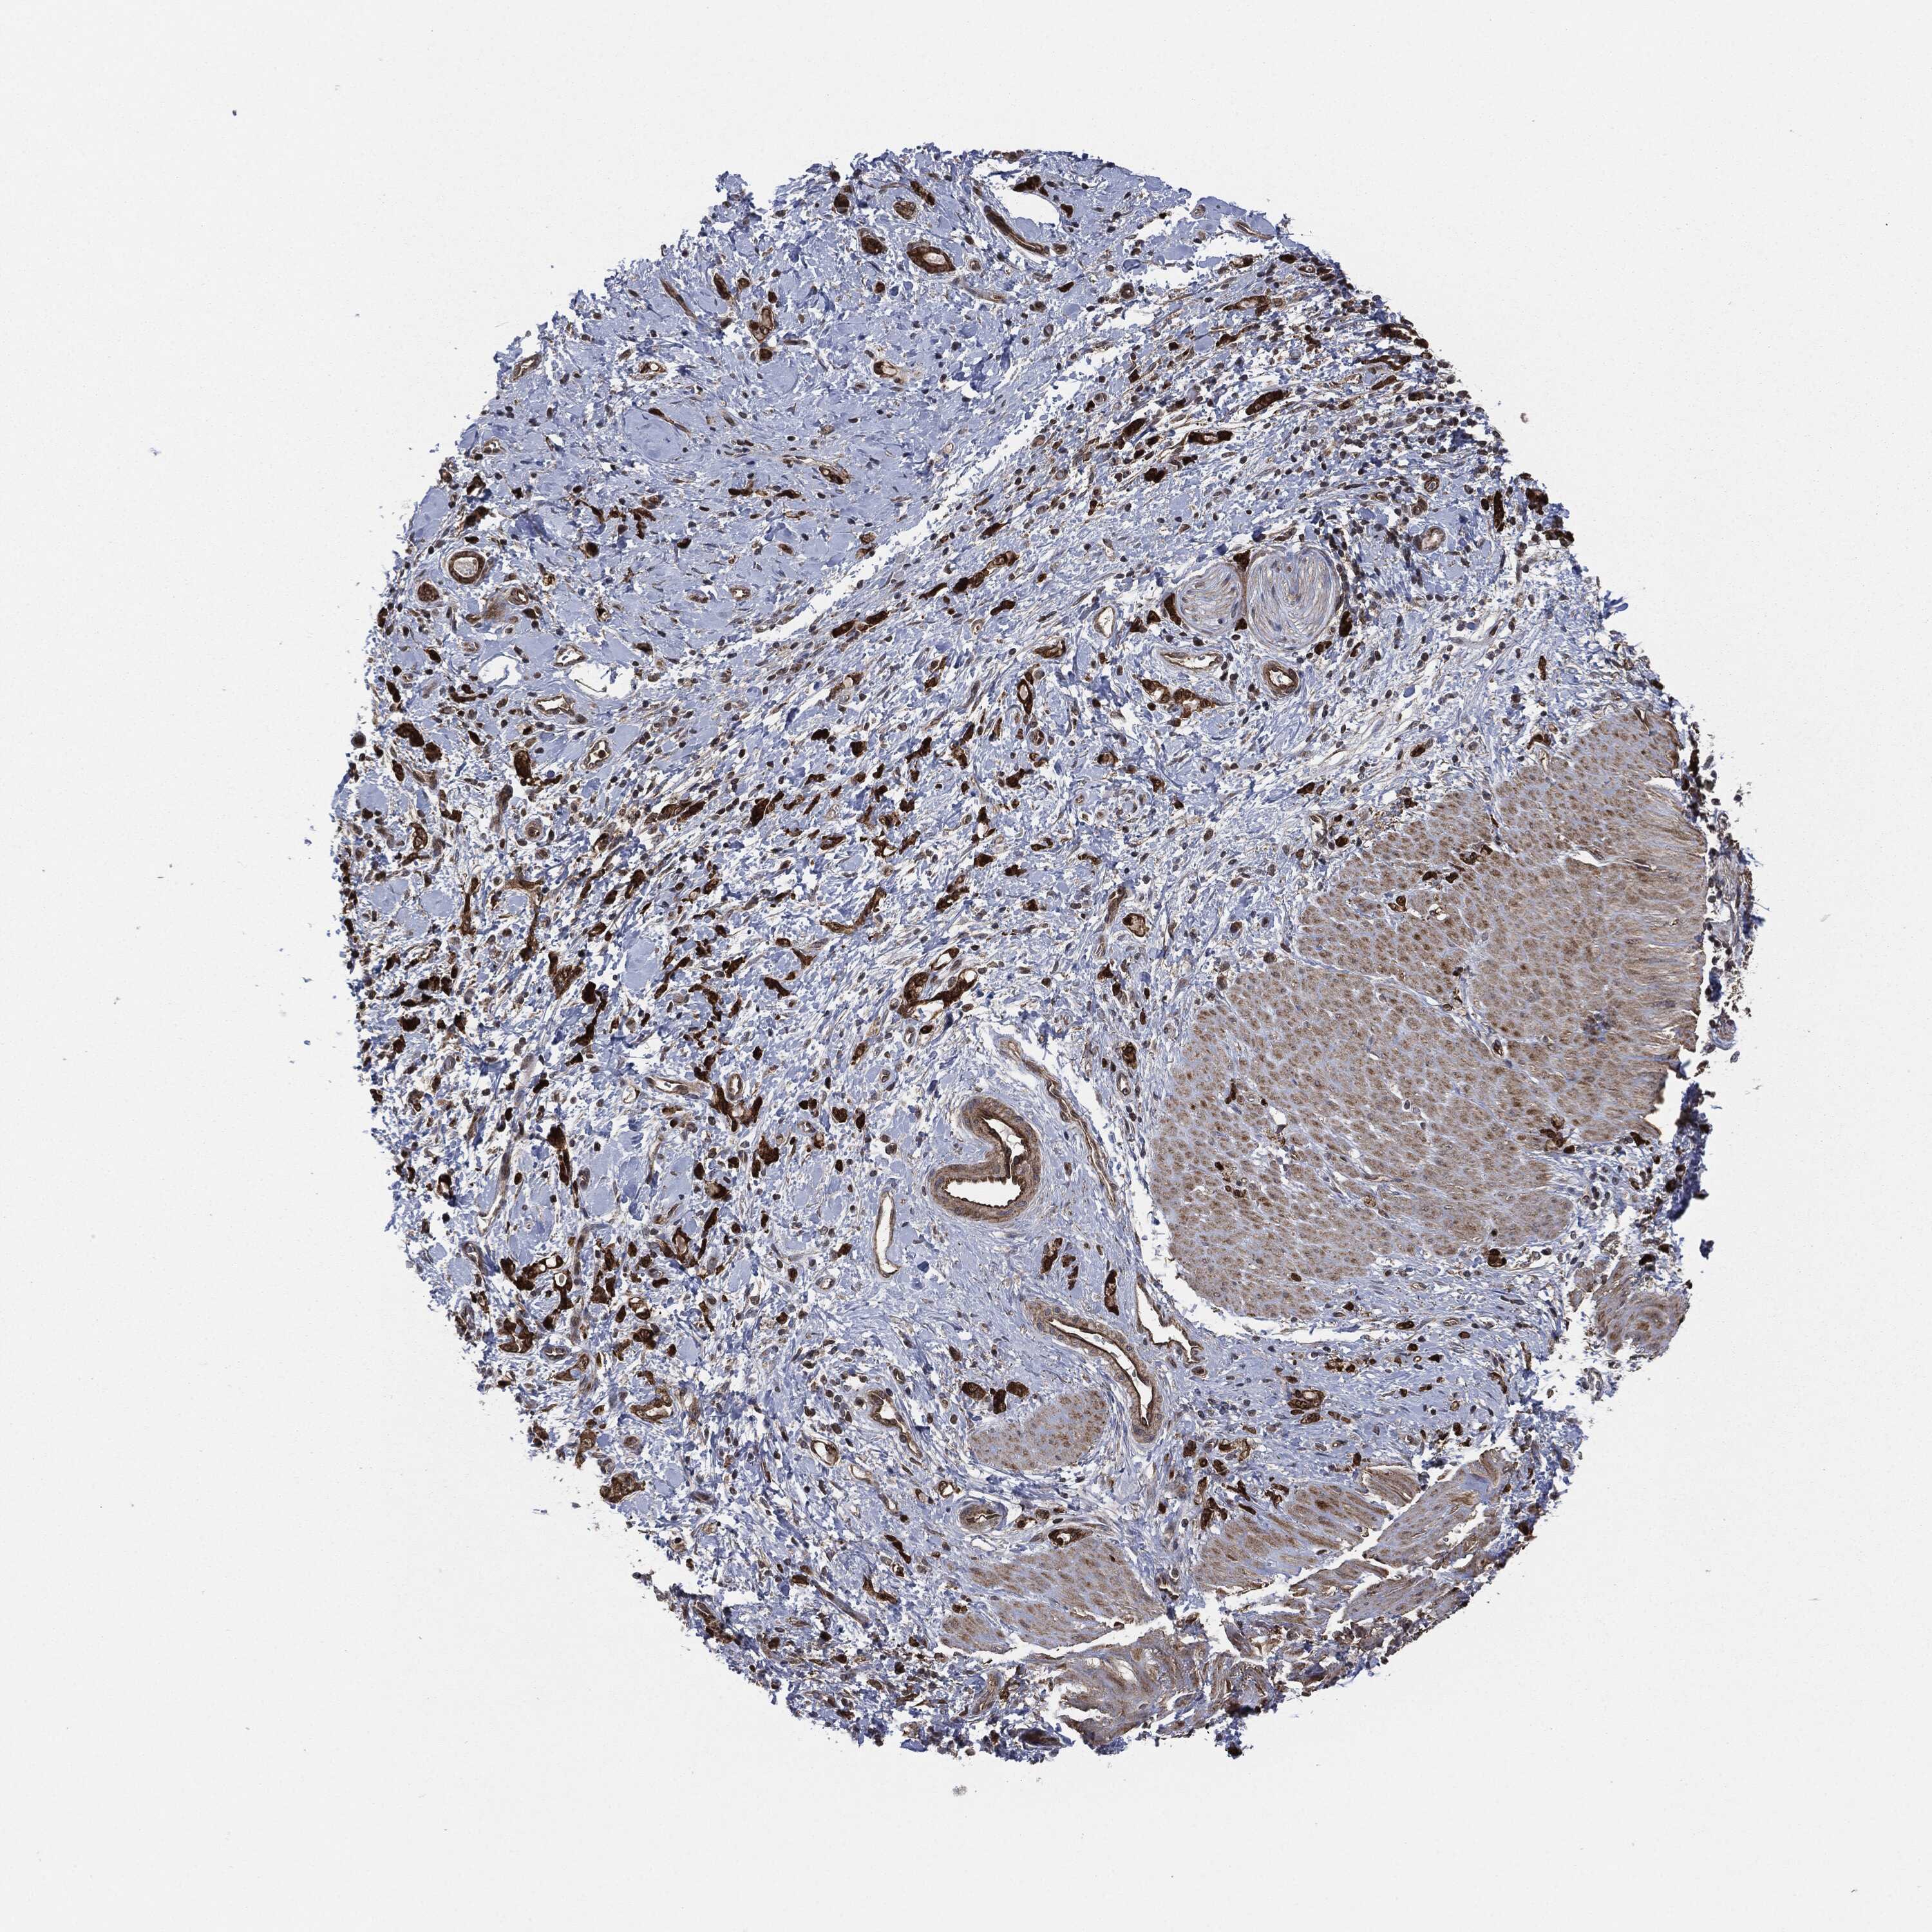

STOMACH CANCER - Protein expressioni

A mouse-over function shows sample information and annotation data. Click on an image to view it in a full screen mode. Samples can be filtered based on level of antibody staining by selecting one or several of the following categories: high, medium, low and not detected. The assay and annotation is described here.

Note that samples used for immunohistochemistry by the Human Protein Atlas do not correspond to samples in the TCGA dataset.

Antibody stainingi

Antibody staining in the annotated cell types in the current human tissue is reported as not detected, low, medium, or high, based on conventional immunohistochemistry profiling in selected tissues. This score is based on the combination of the staining intensity and fraction of stained cells.

Each image is clickable and will lead to virtual microscopy that enables deeper exploration of all samples and also displays staining intensity scores, fraction scores and subcellular localization as well as patient and tissue information for each sample.

Staining

High

Medium

Low

Not detected

Intensity

Strong

Moderate

Weak

Negative

Quantity

>75%

75%-25%

<25%

None

Location

Nuclear

Cytoplasmic/membranous

Cytoplasmic/membranous,nuclear

Adenocarcinoma, NOS

Adenocarcinoma, High grade